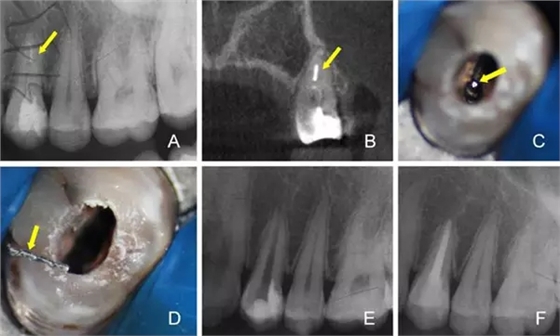

8.webp.jpg

A:術(shù)前X線根尖片 B:術(shù)前CBCT定位折斷器械位置 C:顯微鏡下尋找折斷器械 D:顯微鏡下隱裂紋清晰可見 E:術(shù)后X線根尖片 F:一年后復查X線根尖片